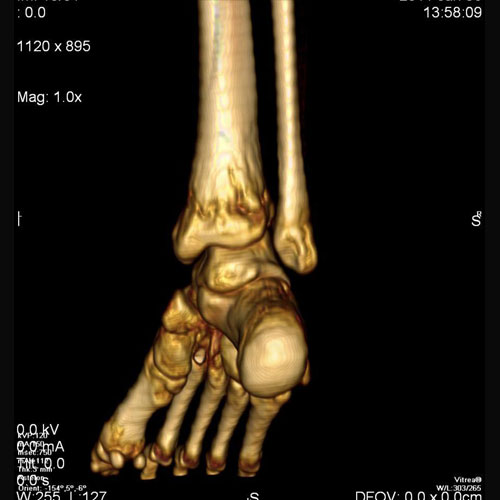

15 year old boy with pain at ankle.

CT with 3D reconstruction shows Osteomyelitis at distal metaphysis of tibia.